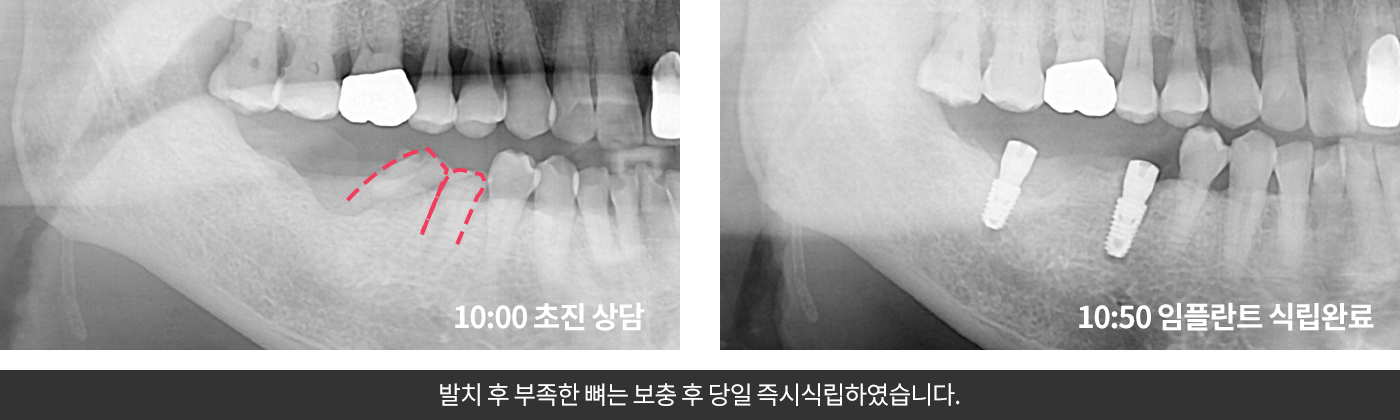

발치해야하는치아를 뽑은 직후 필요시 잇몸뼈까지 이식 후 임플란트를 식립하는 방법입니다.

발치를 한 즉시 임플란트 픽스쳐를 식립하기 때문에

발치 후 회복을 거쳐야하는 기존의 임플란트 방식보다 빠르고 안정적입니다.